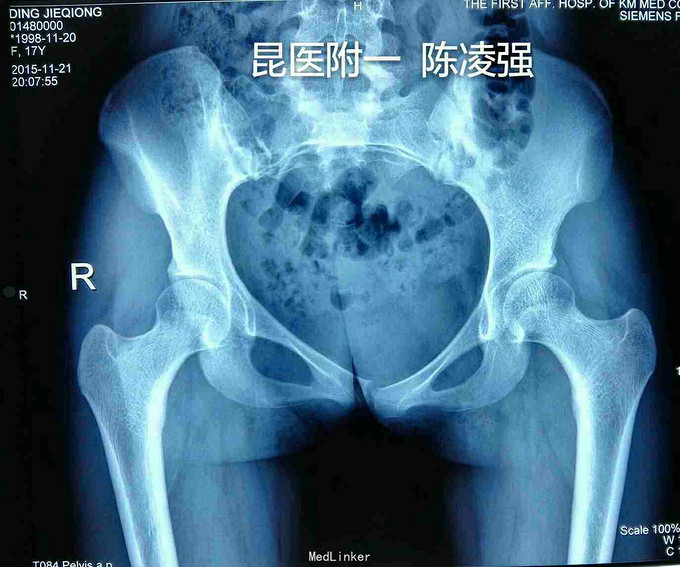

17岁,女,学校跳高运动时臀部着垫致骶尾部疼痛1天

骶骨1-3右侧压痛,无下肢感觉运动障碍,会阴区无感觉异常,肛门括约肌无异常

骶骨肿瘤(倾向低度恶性),右侧骶髂关节破坏 肿瘤刮切+骨块植骨骨水泥填充放射粒子植入+腰4-髂骨固定术 术中冰冻认为 梭型细胞,稍显异型性,恶性不排